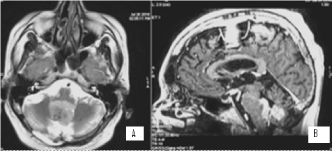

It concerns a female patient of 48 years of age diagnosed with a 10-year-old invasive intraductal carcinoma of the right mammary glands /рТ2N0M0, G2, positive estrogen and progesterone receptors, HER2/+ + +. Surgery (quadrantectomy with axillary dissection), adjuvant chemotherapy, radiotherapy of right mammary gland with operative scarring to OOD 50 Gy, endocrine therapy, targeted therapy with Herepectin was conducted. Two years after the diagnosis, local relapse is manifests, surgically removed by a simple mastectomy with subsequent healing PCT, herepectin and endocrine therapy. In the next 8 years, a consistent solitar liver and pulmonary metastases are diagnosed sequentially, which are surgically removed. Patient aminess continues systemic chemotherapy (SC) and target therapy. On the occasion of an epileptic seizure, after the CT of the brain with venous contrast, the infra- and subtenorial metastasis in the cerebrum is established. The MRI of neuroaxial reports leptomeningeal brain metastases, mainly infratentorial in the cerebellum and medulla oblongata, with mild compression of the brainstem. The spinal axis is not engaged (Figures 5 and 6).

Figure 5. A/SAG T1 FLAIR MRI; B/ AX T1 FLAIR MRI and C/COR T1 FLAIR MRI- postcontrast images showing hyperintense leptomeningeal brain lesions, mainly infratentorial in the cerebellum and medulla oblongata, with mild compression of the brainstem

Figure 6. SAG T2 MR images without pathological lesions in the spinal cord

It was assessed for whole brain radiotherapy (WBRT) to ТD 40 Gy with DFD 2 Gy, which is currently being conducted, after which target therapy will be conducted.